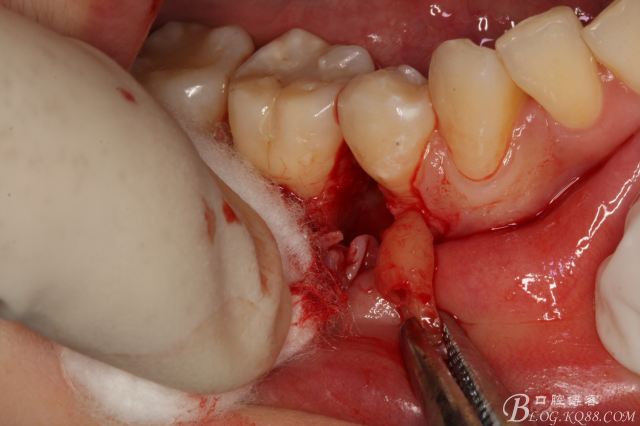

圖12.微創(chuàng)牙挺放入制備好的溝槽內(nèi)。

圖13.取出一塊牙根。給余留 牙根騰出脫位空間

圖14.緩慢在余留牙根周圍用挺,挺松45余留牙根